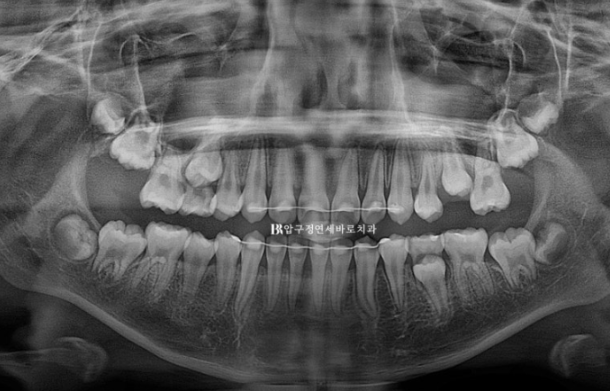

소아교정을 위해 찾아온 만 9세 어린이 입니다.

엑스레이를 보면 아직 유치가 8개나 남아있긴 합니다만 보증기간인 18개월 후면 영구치도 대부분 나올 것으로 예상이 됩니다.

뿌리 평행도 역시 좋습니다.